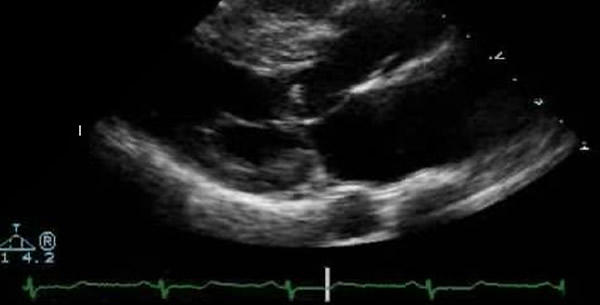

Kod 60% se nasljeđuje autosomno dominantno. Kod ostalih se nasljeđivanje ne može dokazati. Patohistološki nalazimo asimetričnu distrubuciju hipertrofije u 90% pacijenata, zadebljanje endokarda, interventrikularnog septuma i abnormalnost intramuralnih koronarnih arterija. Histološki vidimo difuzno narušenu građu miokarda. Kod većine oboljelih je prisutna obstrukcija izlaznog trakta iz lijevog ventrikula što je rezultat abnormalnog pokreta prednje mitralne valvule.

Sa obstrukcijom (tipična IHSS) prekordij je hiperaktivan, mezosistolni ejekcioni šum pojačava se na inhalaciju amil nitrita. Kod 70% djece je šum na donjem rubu sternuma. Bez obstrukcije nalaz je diskretan, sistolni šum je blag.

- Rtg snimak srca-kod 2/3 pacijenta kardiomegalija, nekada evidentno uvećanje lijevog atrija.